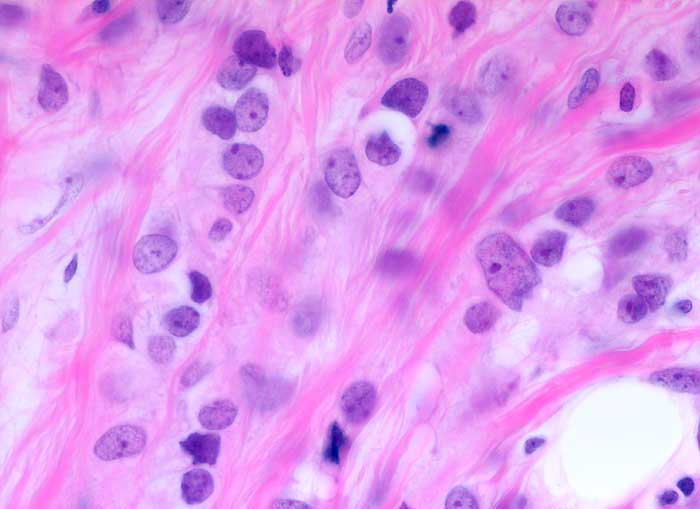

PathoPic ID 5600 - invasiv lobuläres Mammakarzinom

invasiv lobuläres Mammakarzinom

maligner Tumor

Mamma

In Einerreihen hintereinander gänsemarschartig angeordnete monomorphe kleine Tumorzellen mit geringen Atypien.

Verdacht auf Mammakarzinom

Histologie

630